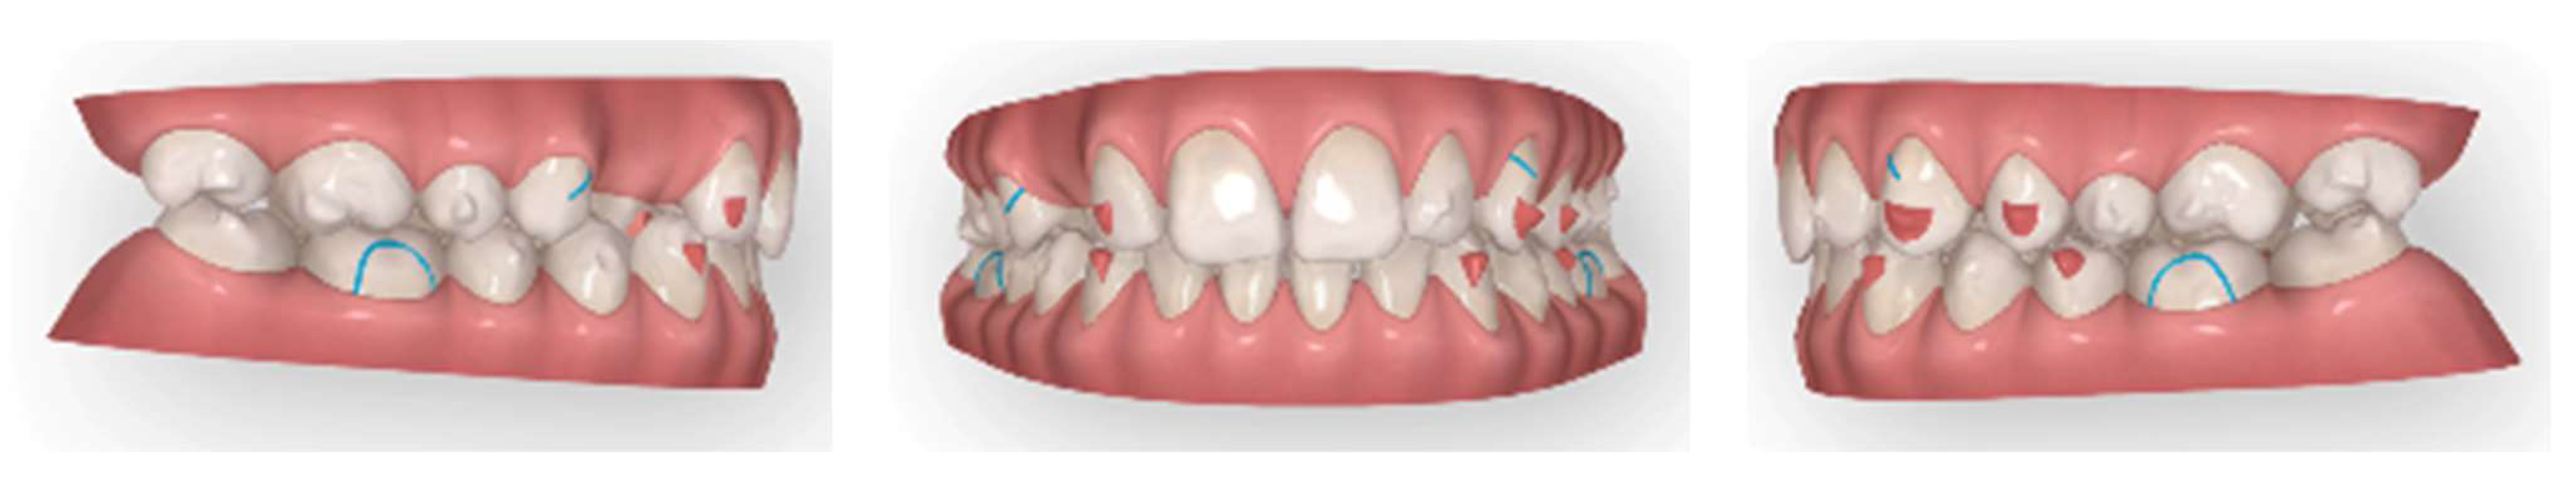

In the first Clincheck®, the use of an eruption compensator was planned in order to locate the displaced canine.

At the same time, the canine was linked to the button cutout of 36 teeth by using Class II elastics to extrude and tip it. On the right side, Class II elastics were placed in order to improve the dental Class II malocclusion (Figure 14 and Figure 15)

Figure 14.

First Clincheck® and the first set of aligners to create space and achieve the alignment and levelling of both arches. Use of elastics and buttons as auxiliaries to promote the extrusion of the impacted canine.

Figure 15.

Progress of treatment with the mechanics of elastics.

Once the displaced tooth was in a better position and near the crest, intraoral impressions and a new series of pictures were taken. Then, an upper arch expansion was planned in order to correct the transverse discrepancy and crowding.

A horizontal rectangular attachment was placed on the buccal surface of the canine, and lingual root torque was applied to ensure the three-dimensional control of the tooth movement (Figure 16).

Figure 16.

Digital impressions after the first set of aligners and a new Clincheck® to refine the occlusion.